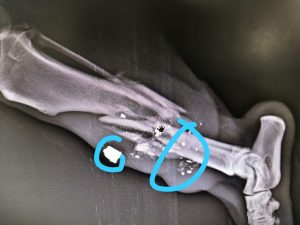

Bolu’dan üç bacağı kırık olarak gelen köpeğimizin, çekilen röntgenler sonrasında bacaklarından kurşunlandığı ortaya çıkmıştır. Maalesef kurşunlar dolayısıyla kemikleri paramparça haldedir. Tedavi süreci başlamıştır.